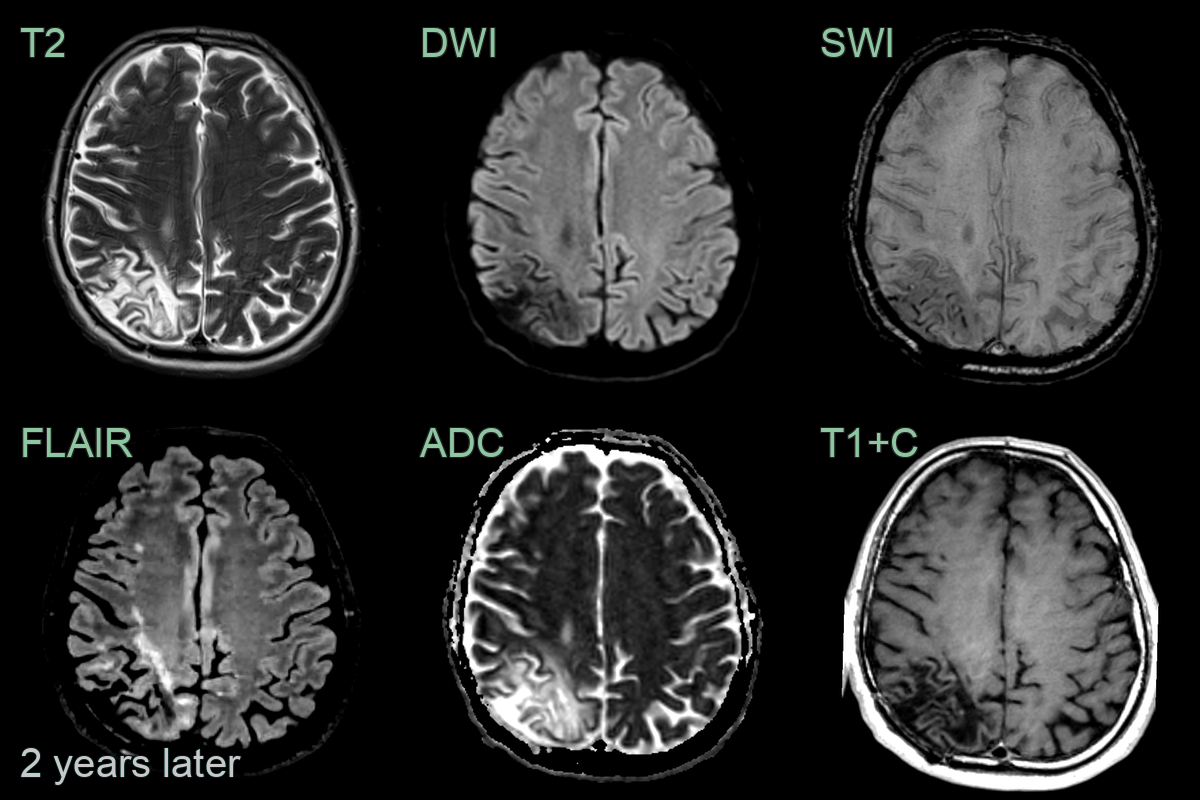

- A 40-year-old patient who had recently underwent CAR-T treatment for lymphoma presented after a 2 week history of headache and photophobia.

- MRI showed a large confluent subcortical region of T2-hyperintensity with a subtle rim of relative diffusion restriction and enhancement.

- Biopsy confirmed PML.

- On follow-up imaging 2 years later, following successful remission of lymphoma, the region matured into a region of gliosis.